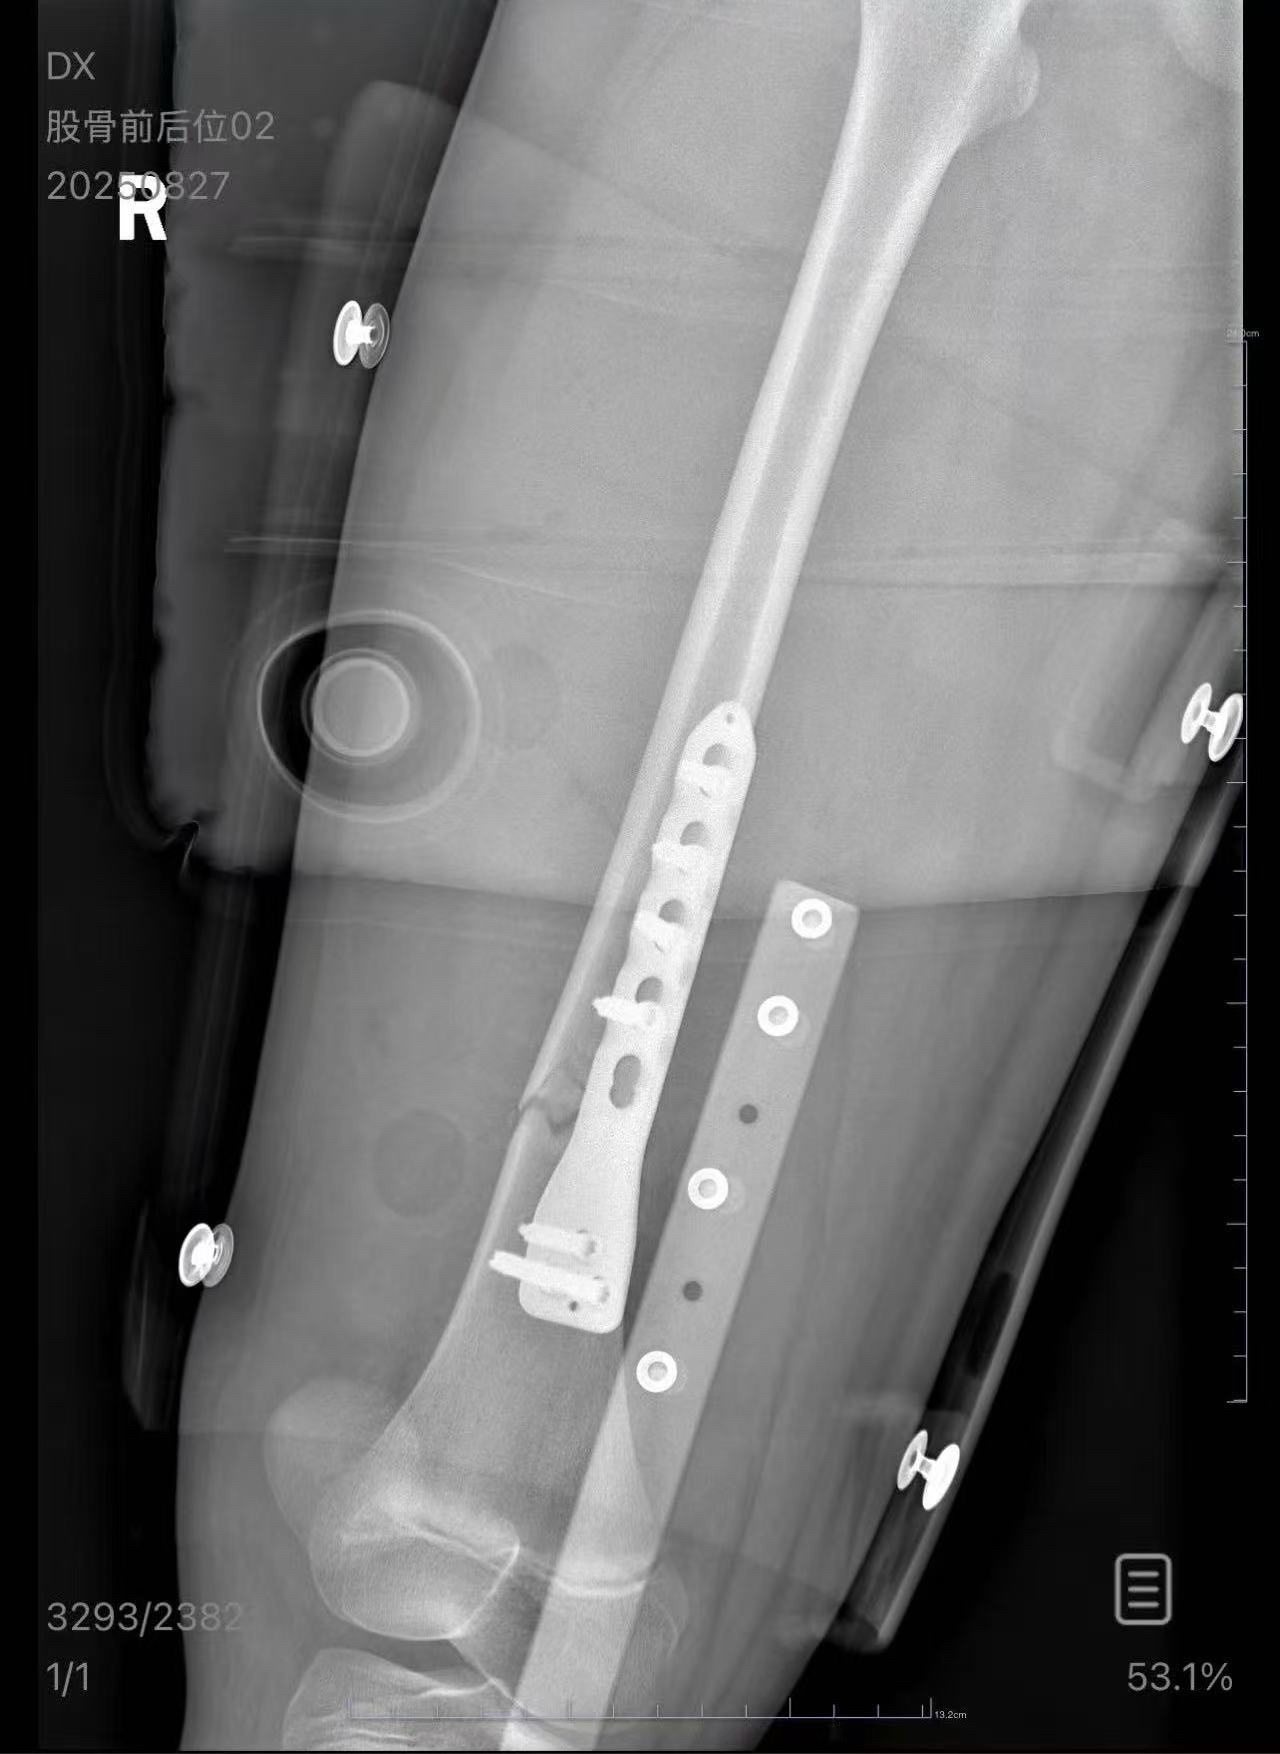

【#男子列车上铺跌落将10岁女孩砸骨折# 女孩母亲:他失去联系,将通过法律途径维权】#男子将10岁女孩砸骨折后失联# 近日,朱女士发帖讲述她今年8月带着孩子乘坐火车时,一名男乘客从上铺摔落,砸到了睡在下铺的孩子的大腿,导致孩子股骨骨折。这名男乘客虽然陪同她们去了医院,但孩子做完手术后,对方表示手头没钱,要回去筹钱。9月上旬,男子最后接了一次朱女士的电话,随后朱女士再也无法联系到对方。